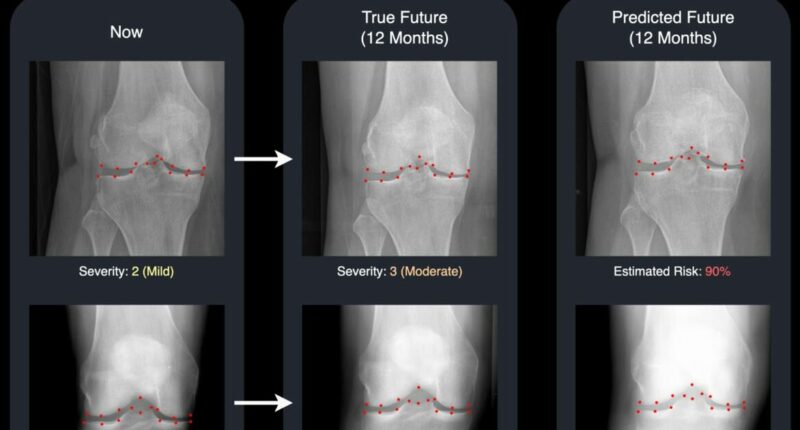

A groundbreaking study from the University of Surrey has introduced a technology that utilizes advanced machine learning techniques to create a realistic “future” X-ray, coupled with a risk score indicating the disease’s progression in the knee. This dual output provides doctors and patients with a clear and visual outlook on how the condition might evolve over time.

Using an advanced generative model, called a diffusion model, the Surrey system generates a “future” version of a patient’s knee X-ray and highlights 16 key points in the joint.

These points add transparency by showing which areas the AI is monitoring for changes, making the system easier for clinicians to understand and trust.

David Butler, leading post-graduate researcher at the University of Surrey’s Centre for Vision, Speech and Signal Processing (CVSSP) and Institute for People-Centred AI, noted: “Typically, medical AI tools provide a numeric prediction with little context.

“Our system goes a step further by not only assessing the likelihood of knee deterioration but also generating a realistic image of what the future condition might appear like.”

“Seeing the two X-rays side by side – one from today and one for next year – is a powerful motivator.